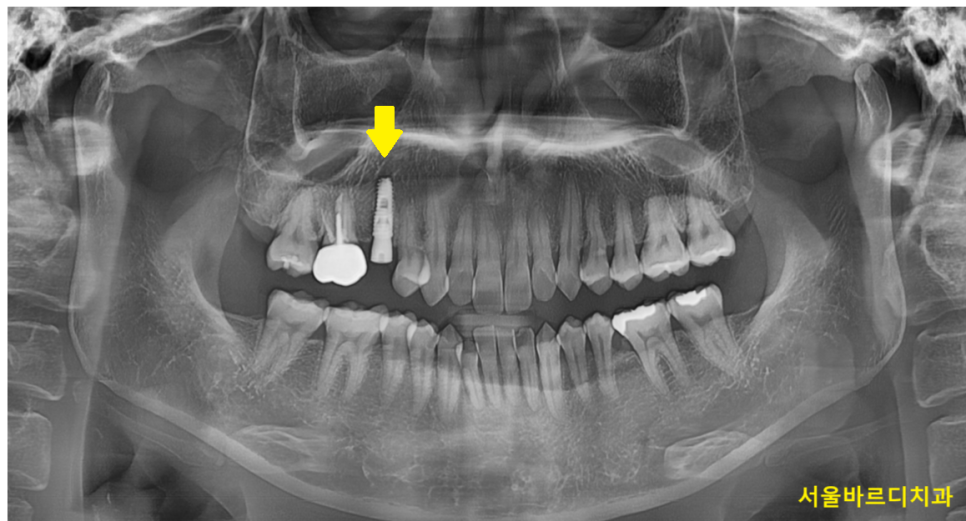

1개를 심는 간단한 임플란트도

ct 촬영을 진행하여

내부 뼈 상태를 확인합니다.

임플란트를 심기 전

뿌리만 남은 경우를 제거 완료하여주고

치아를 뽑은 자리에 임플란트를 식립해줍니다.

다행히 뼈는 충분하여

잇몸 안에 묻어두지 않고 작은 나사를 연결하고 마무리지었습니다.